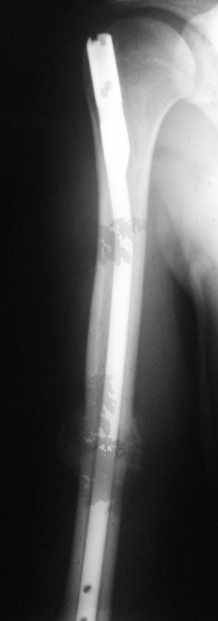

Блокируемый незаблокированный штифт.

Уважаемые коллеги!Обратился пациент, оперирован не у нас.

Что делать?

Варианты:

1. Заблокировать.

2. Ничего не делать.

3. Заменить штифт на более толстый.

4. Еще варианты?

однозначно не блокировать и не убирать - есть прекрасная мозоль и все отлично срастается. Мне плохо видно - выступает ли гвоздь проксимально ( кажется, нет, гвоздь строго в уровень с костью)?

Если гвоздь хоть чуть-чуть выступает - убрать гвоздь как можно скорее (месяца через 3 после травмы), если не выступает - оставить все как есть